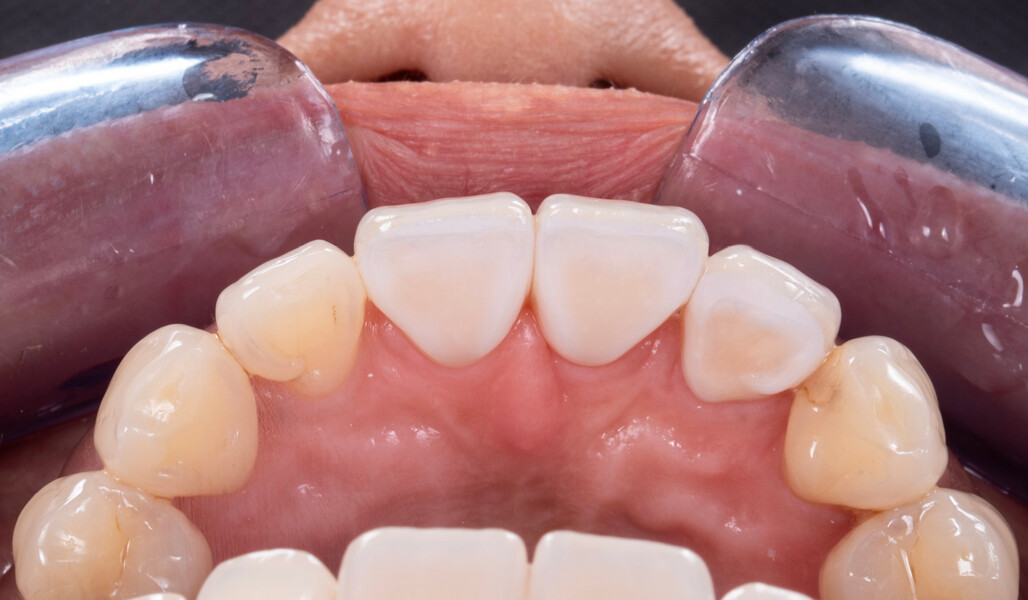

In this article, this point is demonstrated based on the case of a middle-aged female patient who presented with very unsatisfactory metal–ceramic crowns and asked for an aesthetic improvement of the situation (Fig. 1). The crowns on her maxillary central incisors and right lateral incisor clearly needed to be replaced not only for aesthetic reasons but also for functional ones. As anterior interferences were present and orthodontic treatment was not an option, the decision was made to select a ceramic material with a particularly high strength—KATANA Zirconia HT (Kuraray Noritake Dental)—and to opt for a design that would support the incisal edge with zirconia. Consequently, porcelain layering with CERABIEN ZR (Kuraray Noritake Dental) would be limited to the vestibular region (Figs. 2–11).

High-quality materials and a smartly selected design approach laid the foundation for long-term success. Valuable tools used during porcelain layering (specifically the eLAB system) supported the precise reproduction of the patient’s tooth shade, despite the challenging individual aesthetics. Consequently, the crowns were delivered on the first attempt.